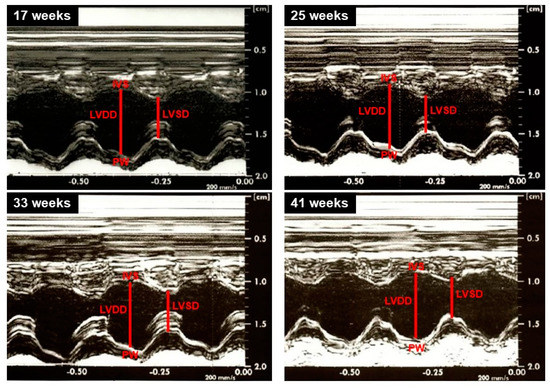

3.3. Cardiac Structural and Functional Assessment